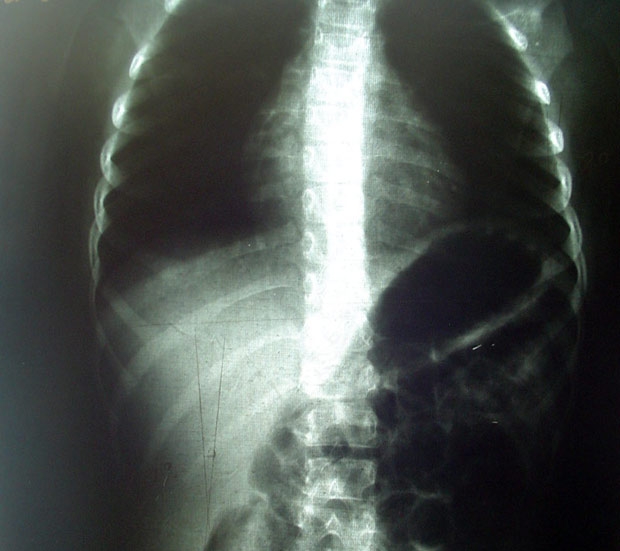

Можно ли справиться с заболеванием без хирургического вмешательства? На текущем этапе симптомы патологии легко устраняются. Обследование начинается с рентгенографии, на которой четко видно искривление позвоночника. Если заболевание обнаруживается у детей, вместо рентгена проводят визуальный осмотр. При сколиозе 1 степени серьезные последствия не возникают, однако родителям следует внимательно следить за осанкой ребенка.

При взгляде фронтально сколиоз первой степени проявляется как наклон спины в сторону. Легкая асимметрия едва заметна. При сколиозе в грудном отделе отмечается небольшая асимметрия лопаток – одна над другой. При локализации в поясничном отделе наблюдается асимметрия таза, талия плохо выражена.